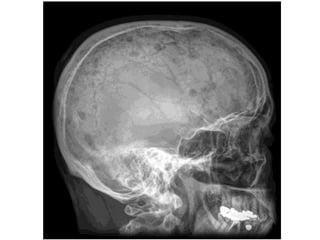

Punched Out” Skill Lesions

• Multiple Myeloma

• Langerhans Cell Histiocytosis

• Metastatic Carcinoma

• Neuroblastoma